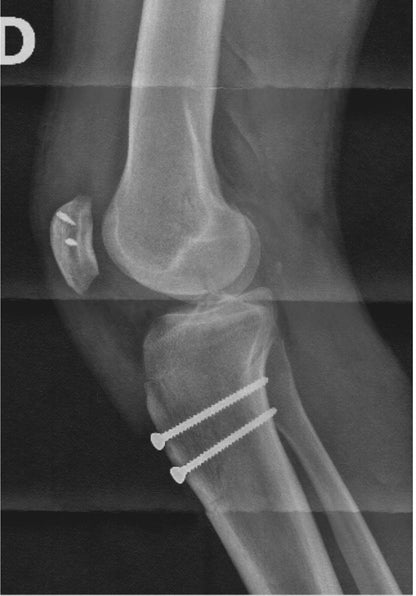

I used a few stills from an MRI and x-ray of my right knee (2 broken joints, torn ligaments, and chipped off some cartilage)..